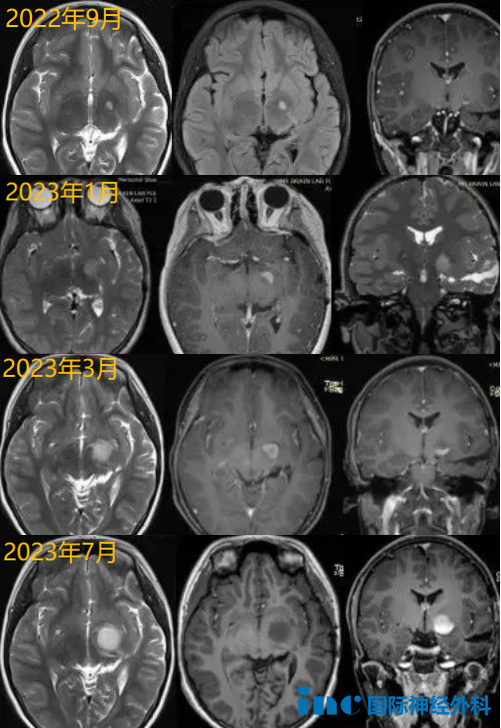

2022年,朋朋在一次常规复查时发现左侧丘脑微小异常信号,手术的医生建议服用靶向药物或化疗,但当时朋朋一家并没有采取任何治疗措施,只是继续通过复查核磁进行观察。

2023年,再次复查MRI显示肿瘤明显增大,于是他们再次咨询了之前的手术医生,医生还是建议服用靶向药物。然而,靶向治疗3个月后,复查MRI显示肿瘤进一步增大和强化。朋朋父母没想到,不到1年时间,这个胶质瘤竟硬生生从米粒大小长到了番茄那么大!